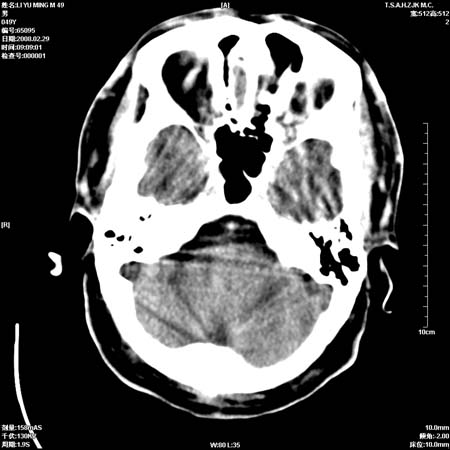

标题: CT12355:男性, 49岁, 主因头痛

男性, 49岁, 头痛, 行ct检查后, 我科一名大夫报了蛛网膜下腔出血, 请大家讨论!

大脑纵裂池及鞍上池应该有蛛血

支持蛛网膜下腔出血。

支持蛛网膜下腔出血